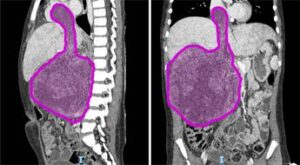

(Adnkronos) - Sei cicli di chemioterapia, poi nove ore di intervento ma ora il tumore di circa 1,5 chili di...